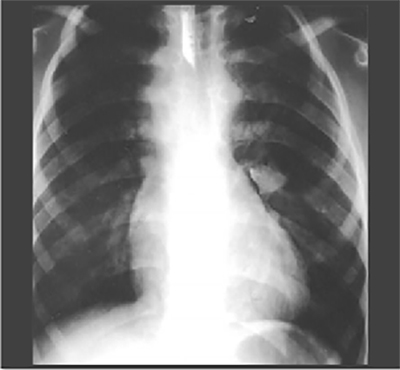

This is the PA chest X ray of our patient. Note the presence of barium in the esophagus in this and subsequent X rays in this program. While no longer used routinely, a barium swallow can reveal pathologic changes. It is presented in this program in the context of teaching anatomic relationships.

Our Patient's PA

Click on the xray to enlarge it.